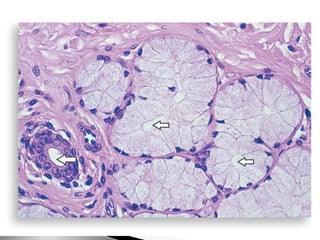

Glándulas alveolares de la próstata, tinción de van Gieson.